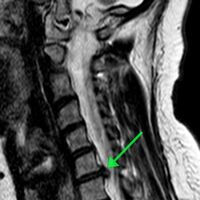

Пациентка обратилась с жлобами на изматывающую боль в руке. Ей провели МРТ, которое показало, что в шейном отделе сформировалась грыжа размером 8 мм. По словам медиков, образование сдавливало спинномозговой канал и корешковое отверстие, угрожая двигательной функции.